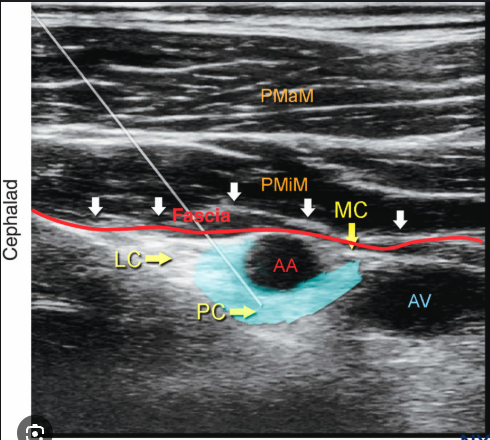

Lumbar plexus

PENG

Interfascial plain block. Does not cover LFC 100 mm needle 20 mL LA